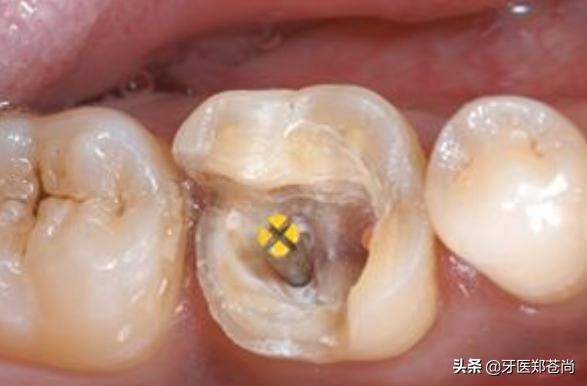

根管治疗是牙体牙髓病的治疗方式,打开牙髓,直达病灶解决问题,但想要完全解决牙齿问题并不仅仅是治疗,治疗后还需要对患牙进行适当的修复,做烤瓷牙或者是嵌体,一方面是为了保护失去牙神经的患牙在以后的吃饭使用中不会崩脆,另一方面是防止外界细菌再进入牙齿内部。

患者提问:我有一颗蛀牙比较严重,之前有医生让我做根管治疗,做了治疗,这颗牙齿还能正常用吗?(患者有一颗重度蛀牙)